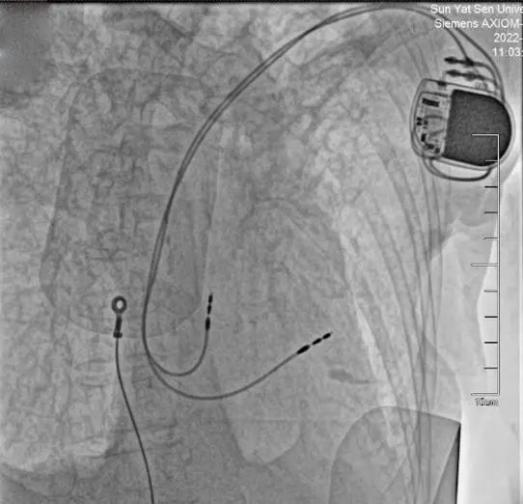

植入心脏起搏器

紧接着,医院麻醉团队实施了精准麻醉,为手术的顺利开展提供了安全保障,仅用时20分钟,就为患者植入了永久性心脏双腔起搏器,植入后起搏器即刻工作,患者心率恢复正常水平。目前,患者术后伤口恢复良好,心率稳定,准备择期出院。